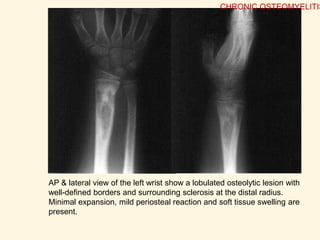

AP & lateral view of the left wrist show a lobulated osteolytic lesion with

well-defined borders and surrounding sclerosis at the distal radius.

Minimal expansion, mild periosteal reaction and soft tissue swelling are

present.

• 55.

AP & lateralview of the left wrist show a lobulated osteolytic lesion with well-defined borders and surrounding sclerosis at the distal radius. Minimal expansion, mild periosteal reaction and soft tissue swelling are present. CHRONIC OSTEOMYELITIS